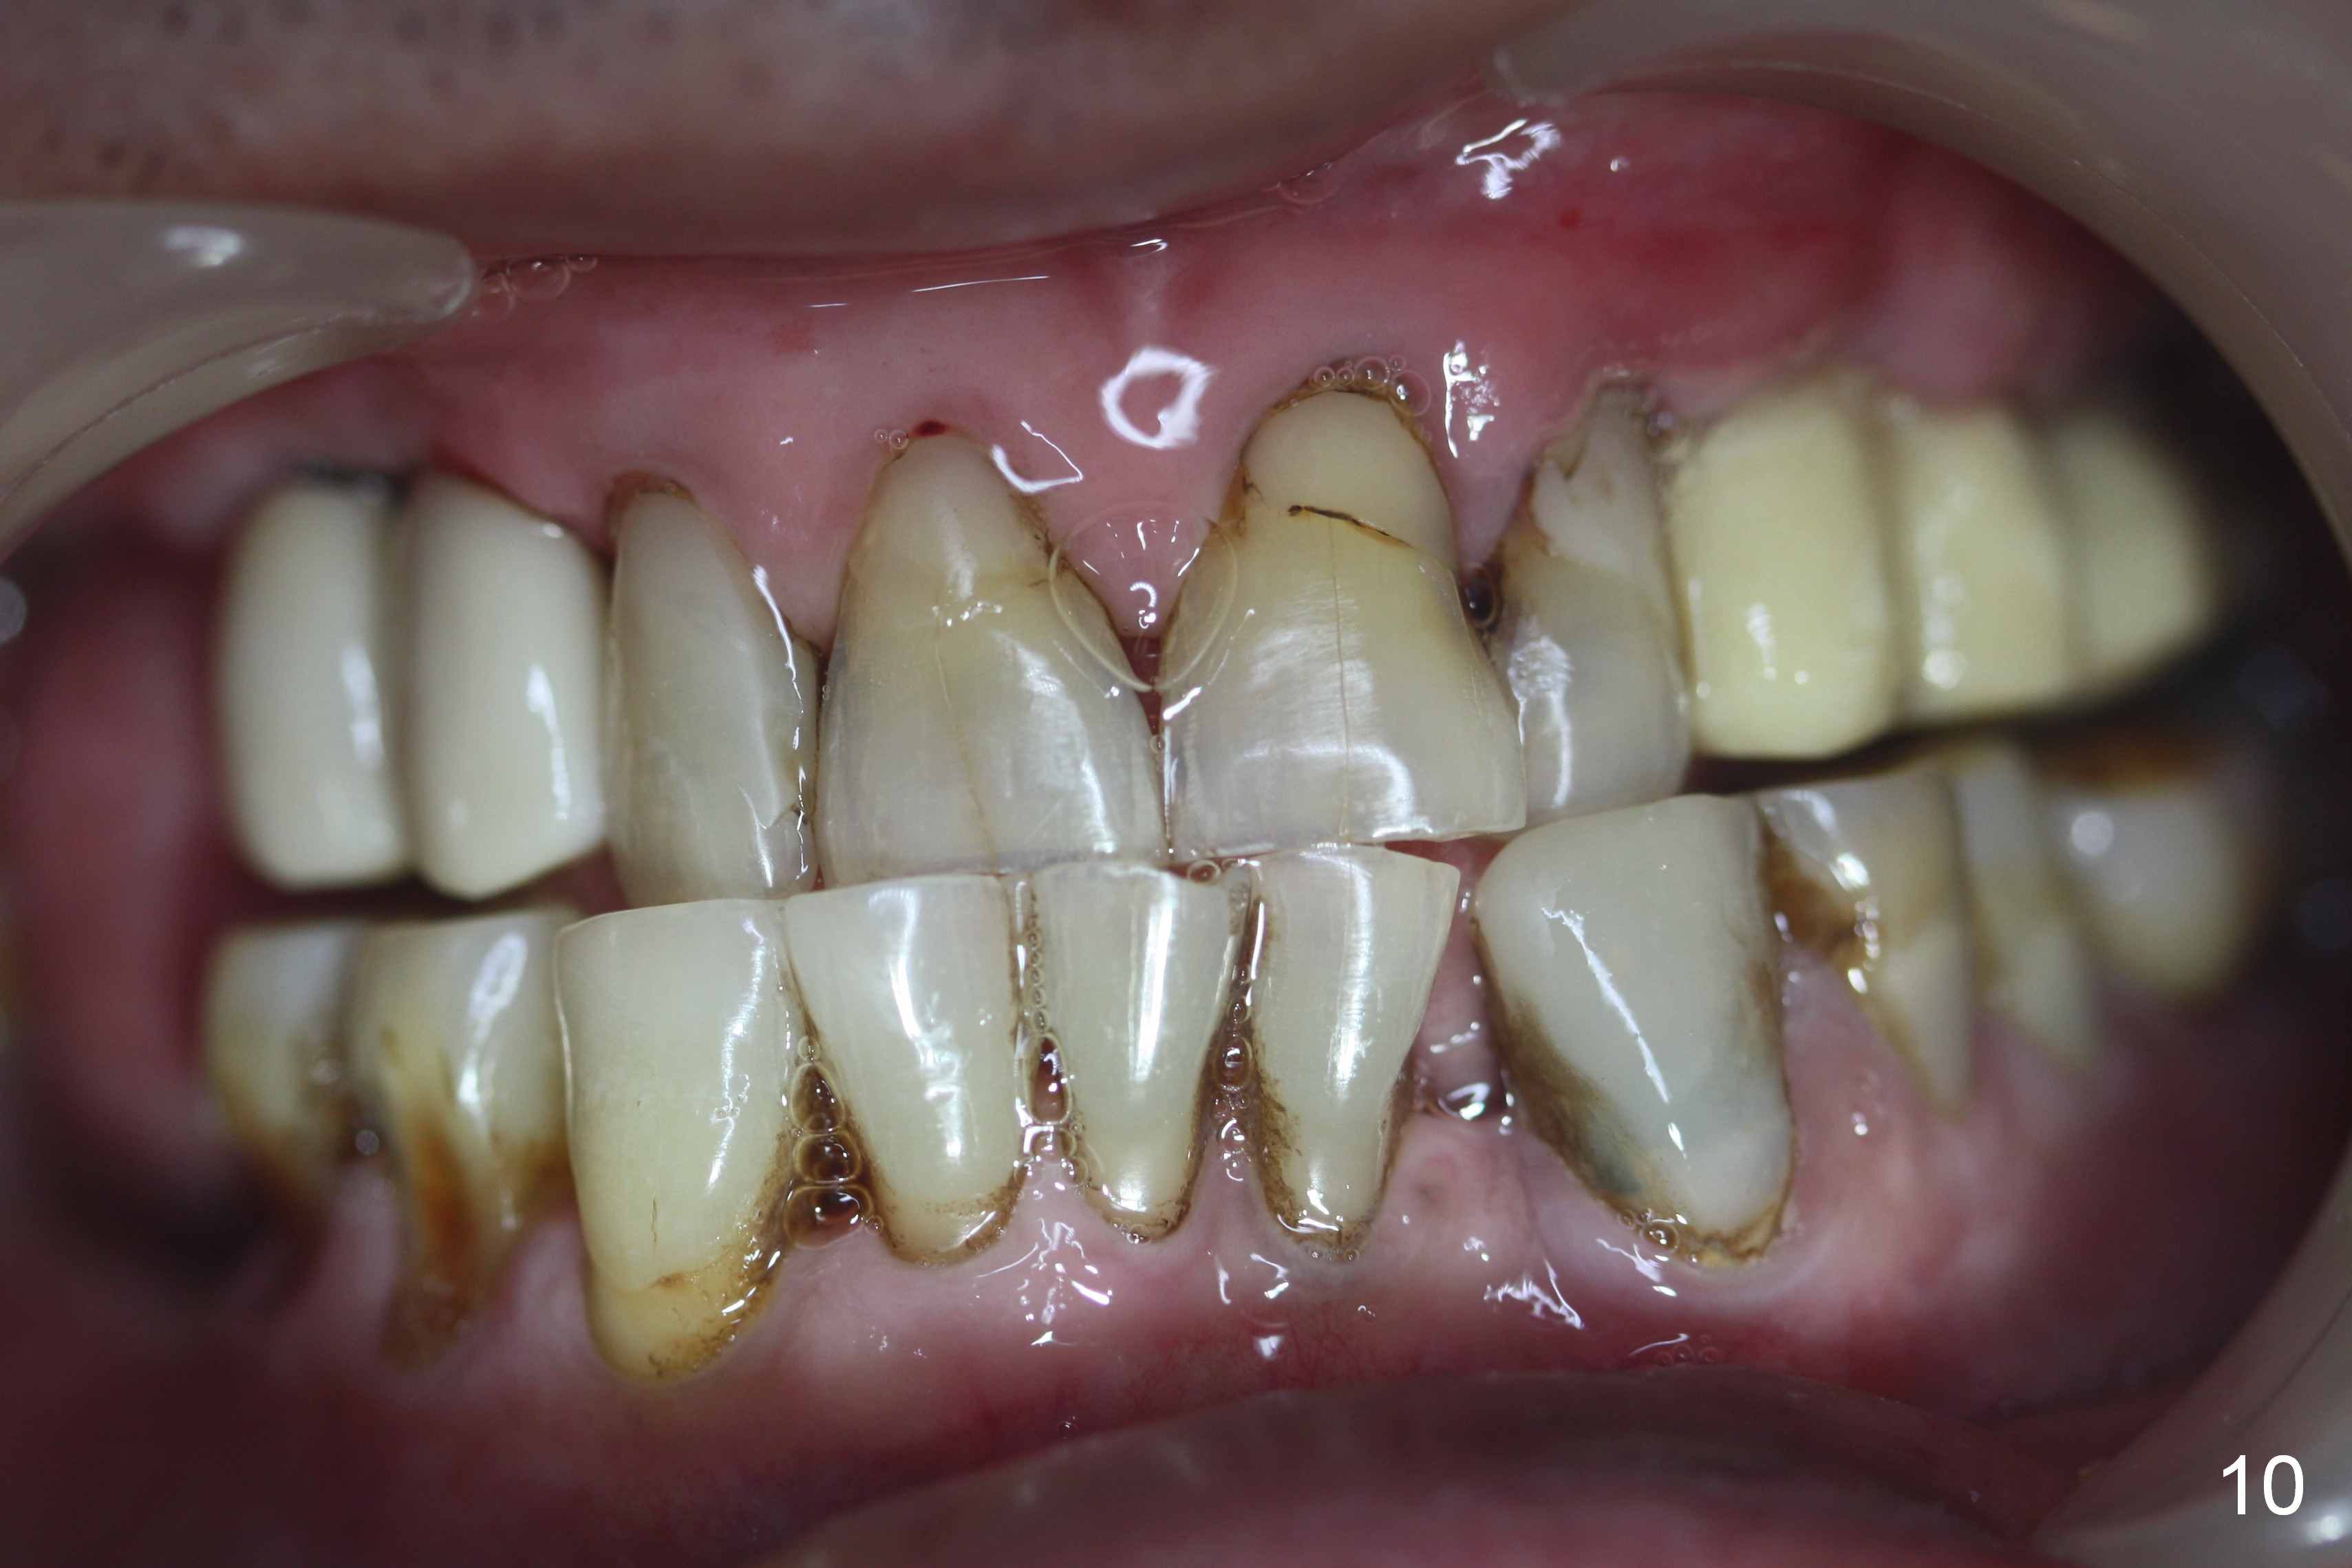

Bone density in the distal gap of #5 appears to have increased 3 months postop (Fig.7). Prior to definitive restoration cementation (3.5 months postop), the buccal plate does not collapse (Fig.8). There is no occlusal contact of the new restorations (Fig.9 *), probably due to bite discrepancy (Fig.10,11).